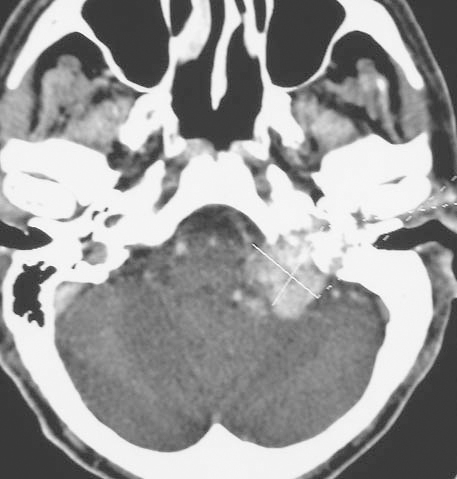

Metody obrazowania w wykrywaniu i monitorowaniu leczenia przyzwojaków nienadnerczowych głowy i szyi

Ocena zastosowania badania tomografii komputerowej (computed tomography – CT) i tomografii rezonansu magnetycznego (magnetic resonance imaging – MRI) w rozpoznawaniu i monitorowaniu leczenia przyzwojaków nienadnerczowych głowy i szyi.